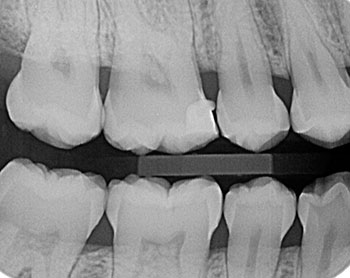

Permite detectar caries interproximales y oclusales, pero también alteraciones pulpares, restauraciones desbordantes, recidivas de caries bajo estas, ajustes de prótesis fijas, cresta alveolar, límite amelocementario; en una misma película se observan las regiones coronal y cervical de los dientes superiores e inferiores a la vez.

Son ideales para detectar caries interproximales y tienen gran aporte en el diagnóstico de enfermedad periodontal.